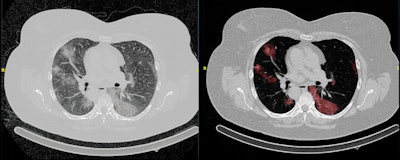

Example of an automated segmentation tool that shows the original image (left) and the predicted segmentation (right). The tool is being used in the Imaging Covid-19 AI research project to develop a deep learning-based model for the automated detection of COVID-19 infection on chest CT and for quantifying lung involvement. The algorithm was trained on a first run of around 1,000 CT scans. Figure courtesy of Quibim.Many recent publications have shown that AI tools, and especially deep learning, can recognize patterns in medical image data with excellent accuracy.